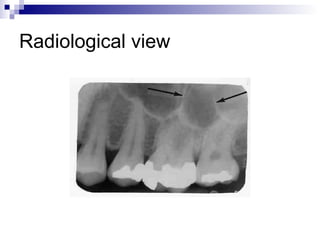

Radiological view

 Adult maxillary sinus averages 34 mm in

anteroposterior direction

 Height= 33 mm

 Width= 23 mm.

 Volume of max sinus=15 to 20 ml.